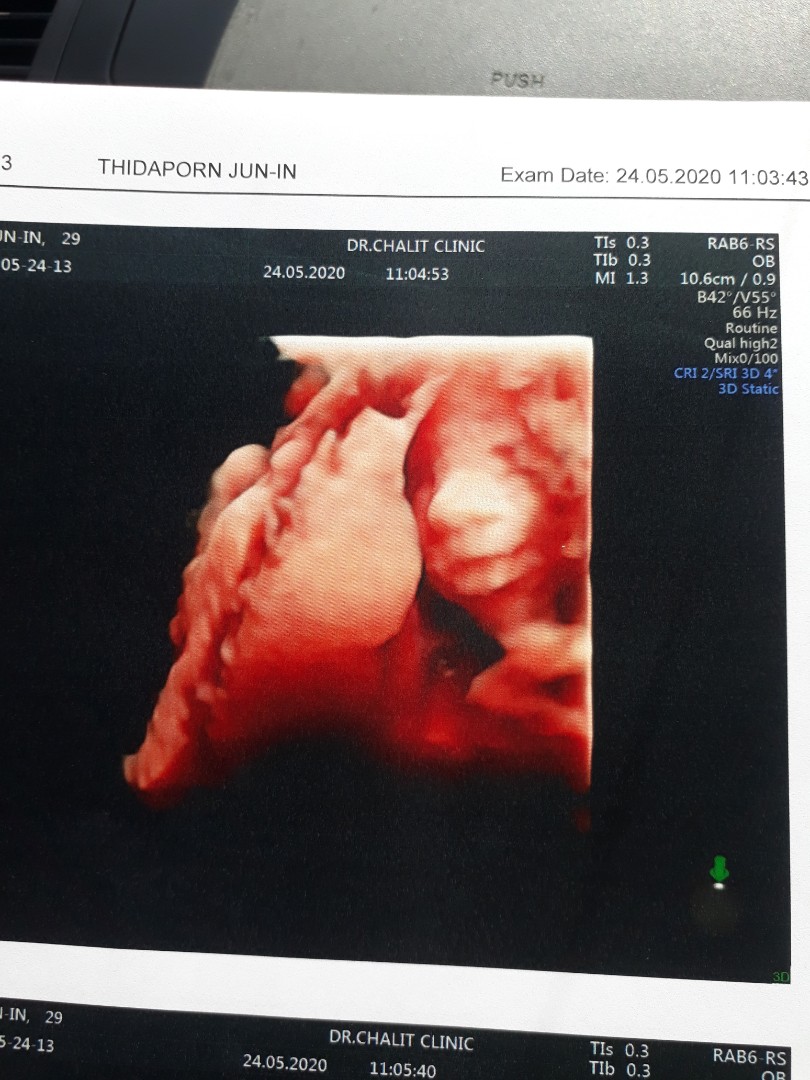

แม่ๆรู้เพศกันเร็วสุดกี่วีคคะ

ท้อง2 ตื่นเต้นมาก อยากได้ลูกสาว ขอดูใบซาวด์บ้านอื่นหน่อยจ้า😍

เห็นเพศตอน19วีคลูกสาวจ้า

ลูกสาวค่ะรุ้ตอน4เดือนค่ะ

20wค่ะหมอบอกลูกสาว